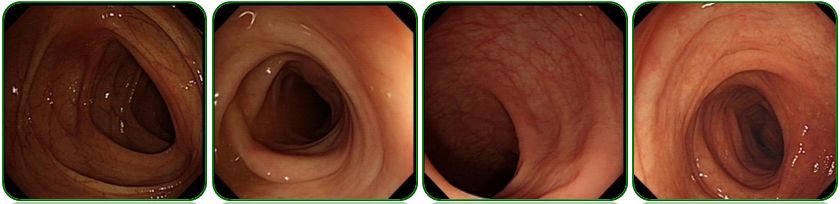

外院胃镜检查见吻合口粘膜充血水肿,残胃未见溃疡及肿物,如图1;

图1 胃镜检查

就在这个时候我们突然发现外院胃镜有点蹊跷,如图1吻合口粘膜有点问题,粘膜粗糙隆起,由于是在外院做的胃镜我们不能全面评估吻合口情况,因此建议患者重新复查胃镜,如图8。复查胃镜发现吻合口前壁黏膜隆起,表面稍粗糙,于是做了病理活检。病理结果提示低分化腺癌,部分为印戒细胞癌。到此为止,该患者诊断才算明确:残胃癌、腹盆腔转移。既然诊断明确了,治疗就有据可依。